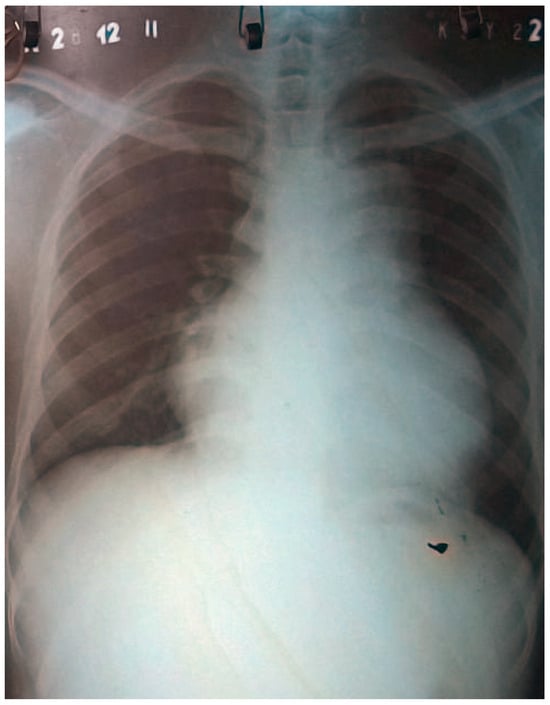

Sixteen days later, the patient complained of worsening of respiratory distress and a complete lack of exercise capacity. The chest X-ray now demonstrated marked enlargement of the heart (Figure 2). The computed tomography (CT) scan revealed a huge false aneurysm originating from the distal ascending aorta and the proximal aortic arch (Figure 3).

Figure 2. Second chest X-ray 16 days later: rapid increase of the cardiothoracic ratio to 0.6.